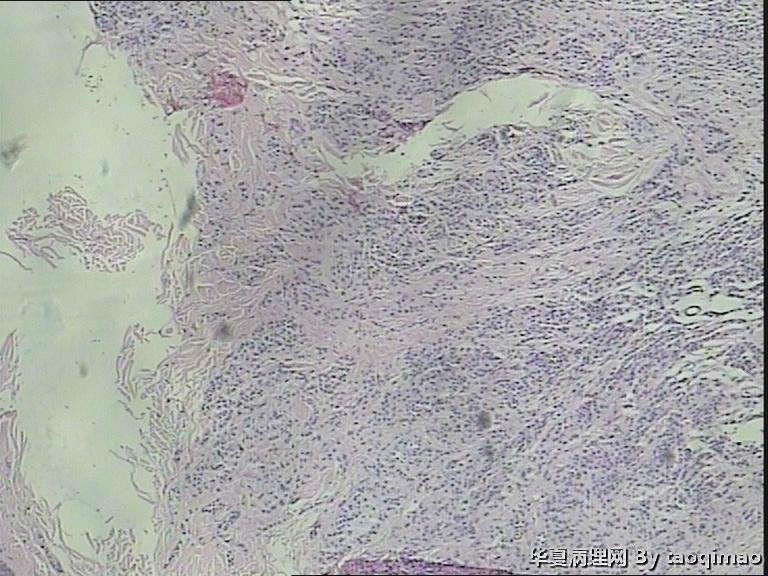

两例头皮肿物有差别么

• 两例头皮肿物有差别么图1

图1

34岁女,头皮肿物,带皮组织一块1x1,皮瓣上可见一灰白结节大小0.6x0.6,皮瓣大小1x0.4 面灰白质软。

门诊患者这一例没有其它更多信息

第一:皮内痣 第二:皮内痣并表皮囊肿

都要考虑皮内痣。实在有差别就是第2例上有表皮囊肿,容易伴发。

皮内痣,第2例伴表皮囊肿,1处于退化期,倒是该学学

但第一例处于退化期了,当然,这没必要写到报告上。

我的问题是为什么是白色的呢,呵呵,我查了些资料没说是白色的

灰白色,我想是由于有的皮内痣本身没有太多色素吧,不少皮内痣是皮色的。你的俩病例,片子里都没啥见到色素,应该可以解释了吧。

头皮皮内痣常呈皮赘样,质软有蒂,很多时候退化后呈正常肤色,切片中常有成熟的脂肪细胞,临床很容易误诊,诊断皮内痣应该没有问题的!